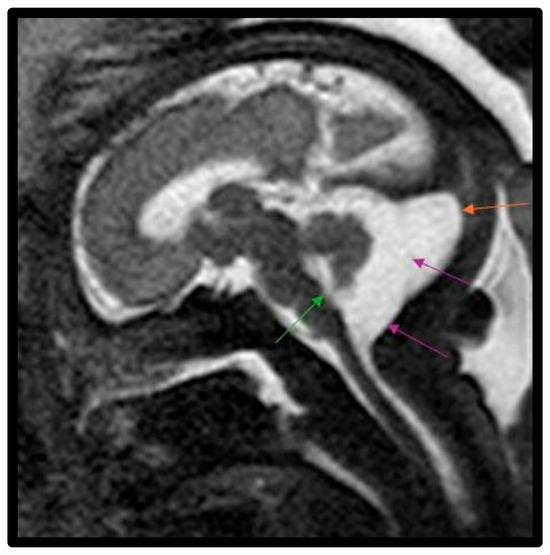

| Vermis AP (mm) * | 10.8 ± 6.2 (n = 6) | 11.8 ± 3.0 | 14.8 (SD, 3.3) | 0.002 |

| TVA (°) * | 93.7° ± 18.1° (n = 6) | 50.9° ± 17.3° | 21.7° (SD, 15.5°) | <0.001 |